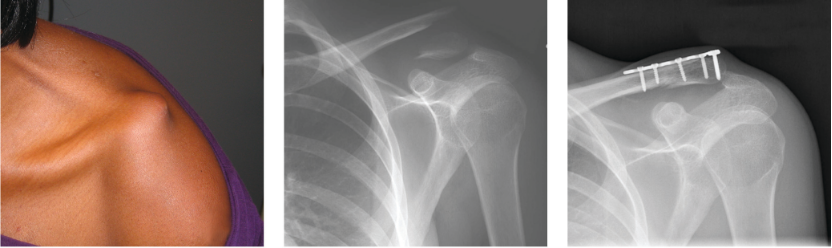

对于不稳定性骨折,手术治疗效果优于保守治疗。下面以图片的形式展示不同的固定方法。

锁骨远端锁定钢板固定

钩钢板用于锁骨远端骨折固定